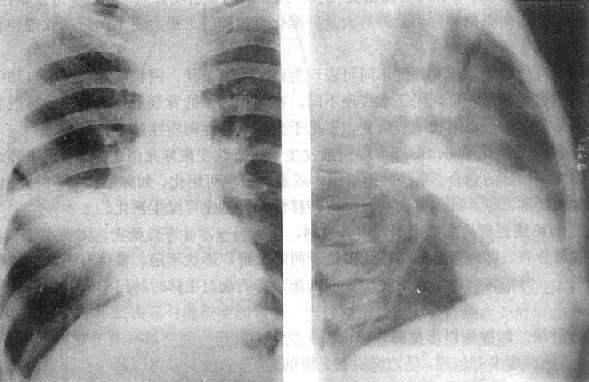

(1)一侧性肺不张:X线现为患侧肺野均匀致密,纵隔向患侧移位,肋间隙变窄(图3-1-7)。健侧肺可有代偿性肺气肿。

图3-1-7 一侧性肺不张

左侧支气管阻塞引起左侧全肺不张,显示左侧肺野均匀致密,

纵隔向患侧移位,肋间隙变窄,膈升高